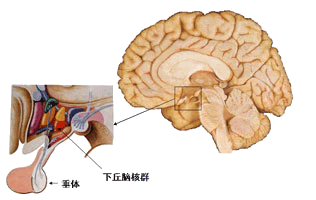

如图所示,间脑由丘脑和下丘脑组成。

2.下丘脑

如图所示,下丘脑位于丘脑前下方,也称丘脑下部,是间脑的一部分。下丘脑是控制自主神经系统的高级中枢,还释放神经激素,通过垂体调节内分泌腺的活动。下丘脑有许多重要的核团,对血压、体温、摄食、水平衡、内分泌调节,具有重要的影响。